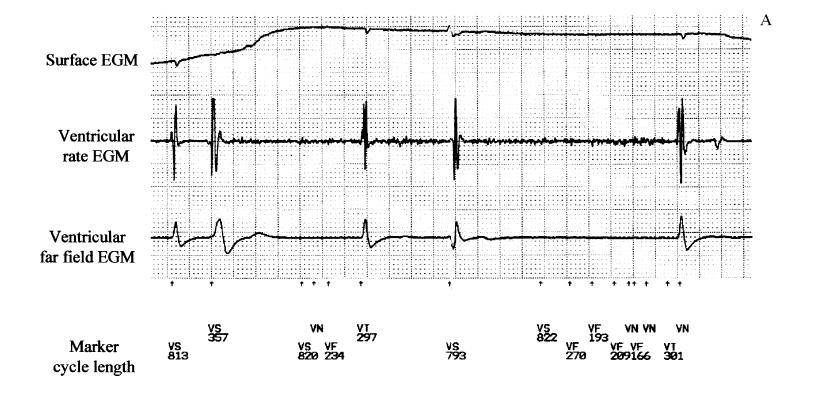

Image of Diaphragmatic Myopotentials

Oversensing of Extracardiac Myopotentials[1] is a well known problem in pacemakers that has been overcome with the use of bipolar sensing leads. Oversensing of diaphragmatic myopotentials(DMP) signals can occur in ICDs and is usually associated with the use of an integrated bipolar lead. Episodes are often seen when during bradycardia in the patient with a intrinsic heart rhythm or in pacemaker dependent patient during pacing.